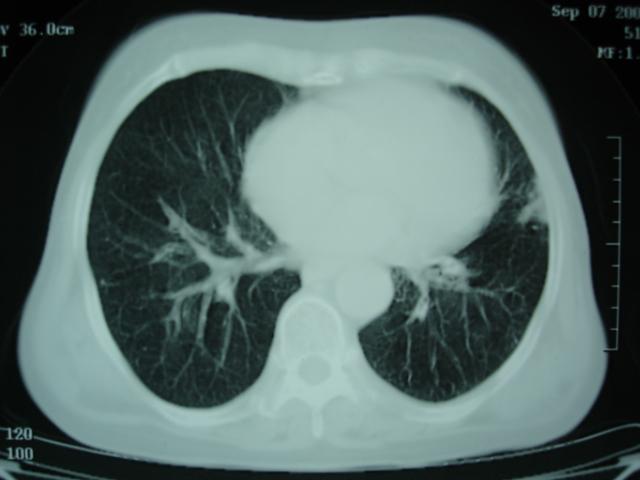

以下是引用卜一在2009-9-7 19:51:00的发言:[br][br] 1 左侧胸内甲状腺占位-多考虑甲状腺腺瘤! 2、左肺门占位-建议增强扫描以便明确性质。 3 慢支并感染! [br]

以下是引用shibing在2009-9-7 20:40:00的发言:[br]左侧胸内甲状腺占位-多考虑甲状腺腺瘤! 2、左肺门占位-建议增强扫描以便明确性质。 3 慢支并感染! [br]